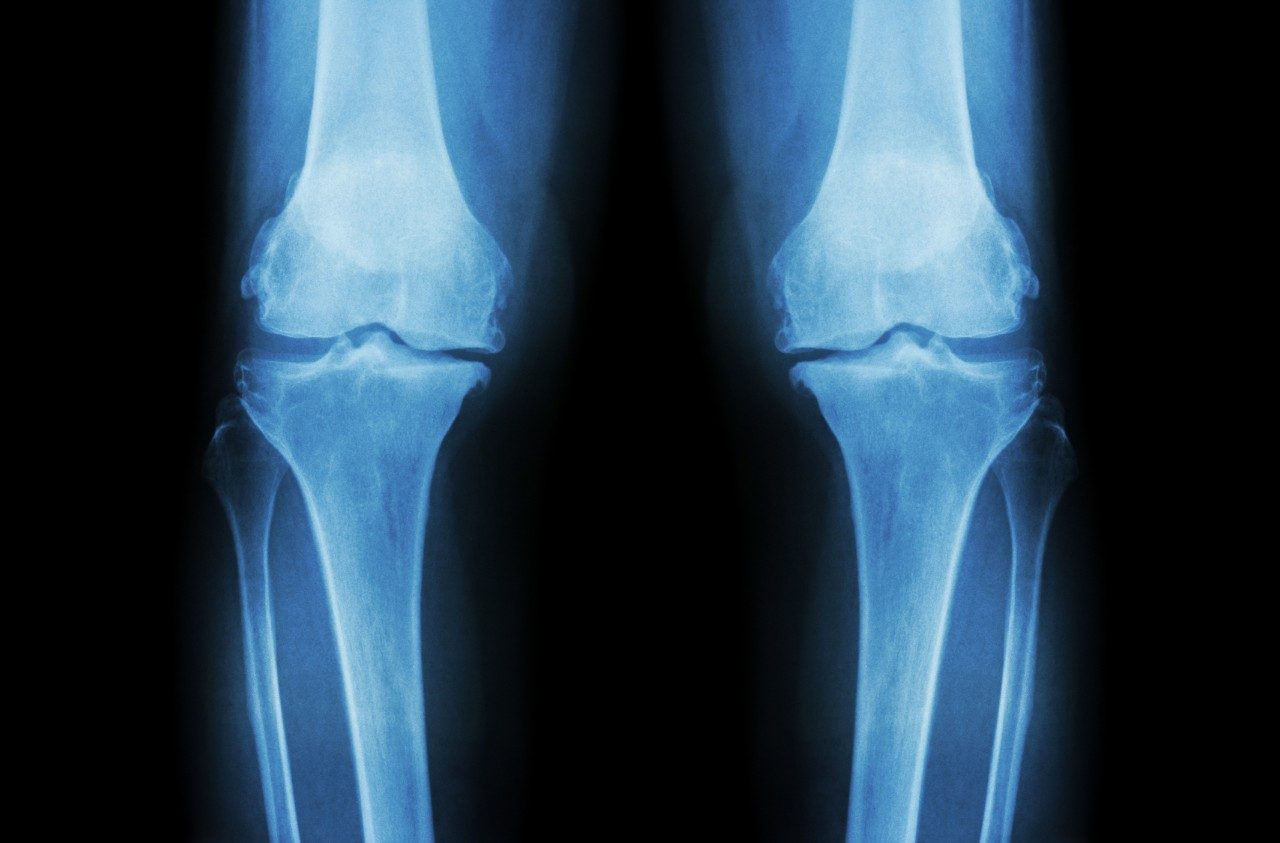

7 things sarcoma patients should know about allografts

For Ewing’s sarcoma and other types of sarcomas, treatment can sometimes include surgery to remove a tumor. That can also mean removing part...